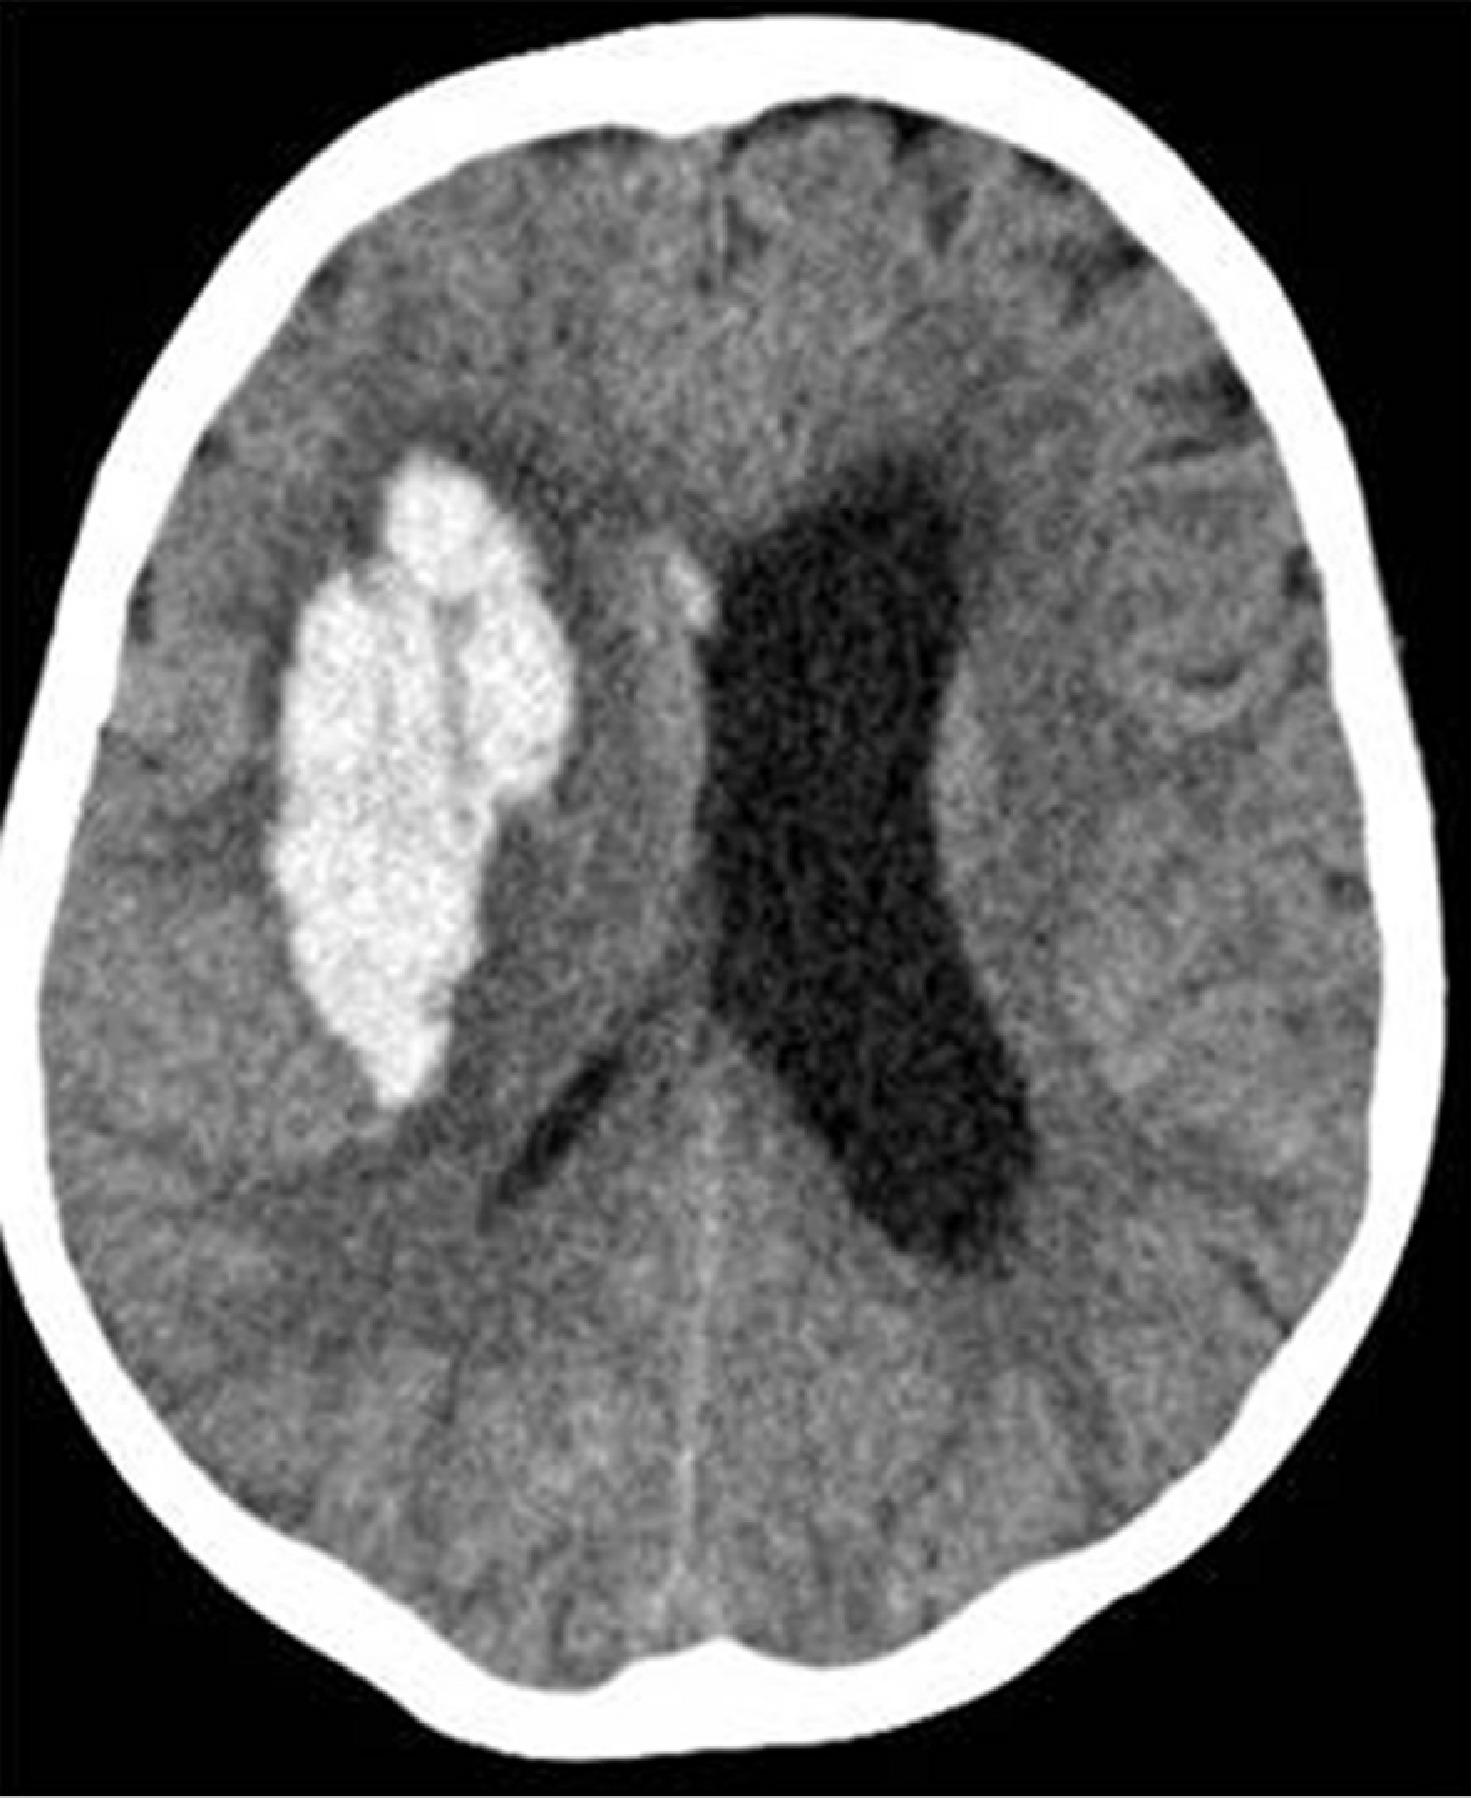

出血性中風

原因多為高血壓或腦血管病變,令血管破裂,血液流出,令腦神經受損。症狀一般來得急而且嚴重,如血液擠壓腦部令壓力升高,可致嚴重頭痛、嘔吐、神志不清,甚至昏迷。必須立即送院,找出出血位置而決定治療方案。